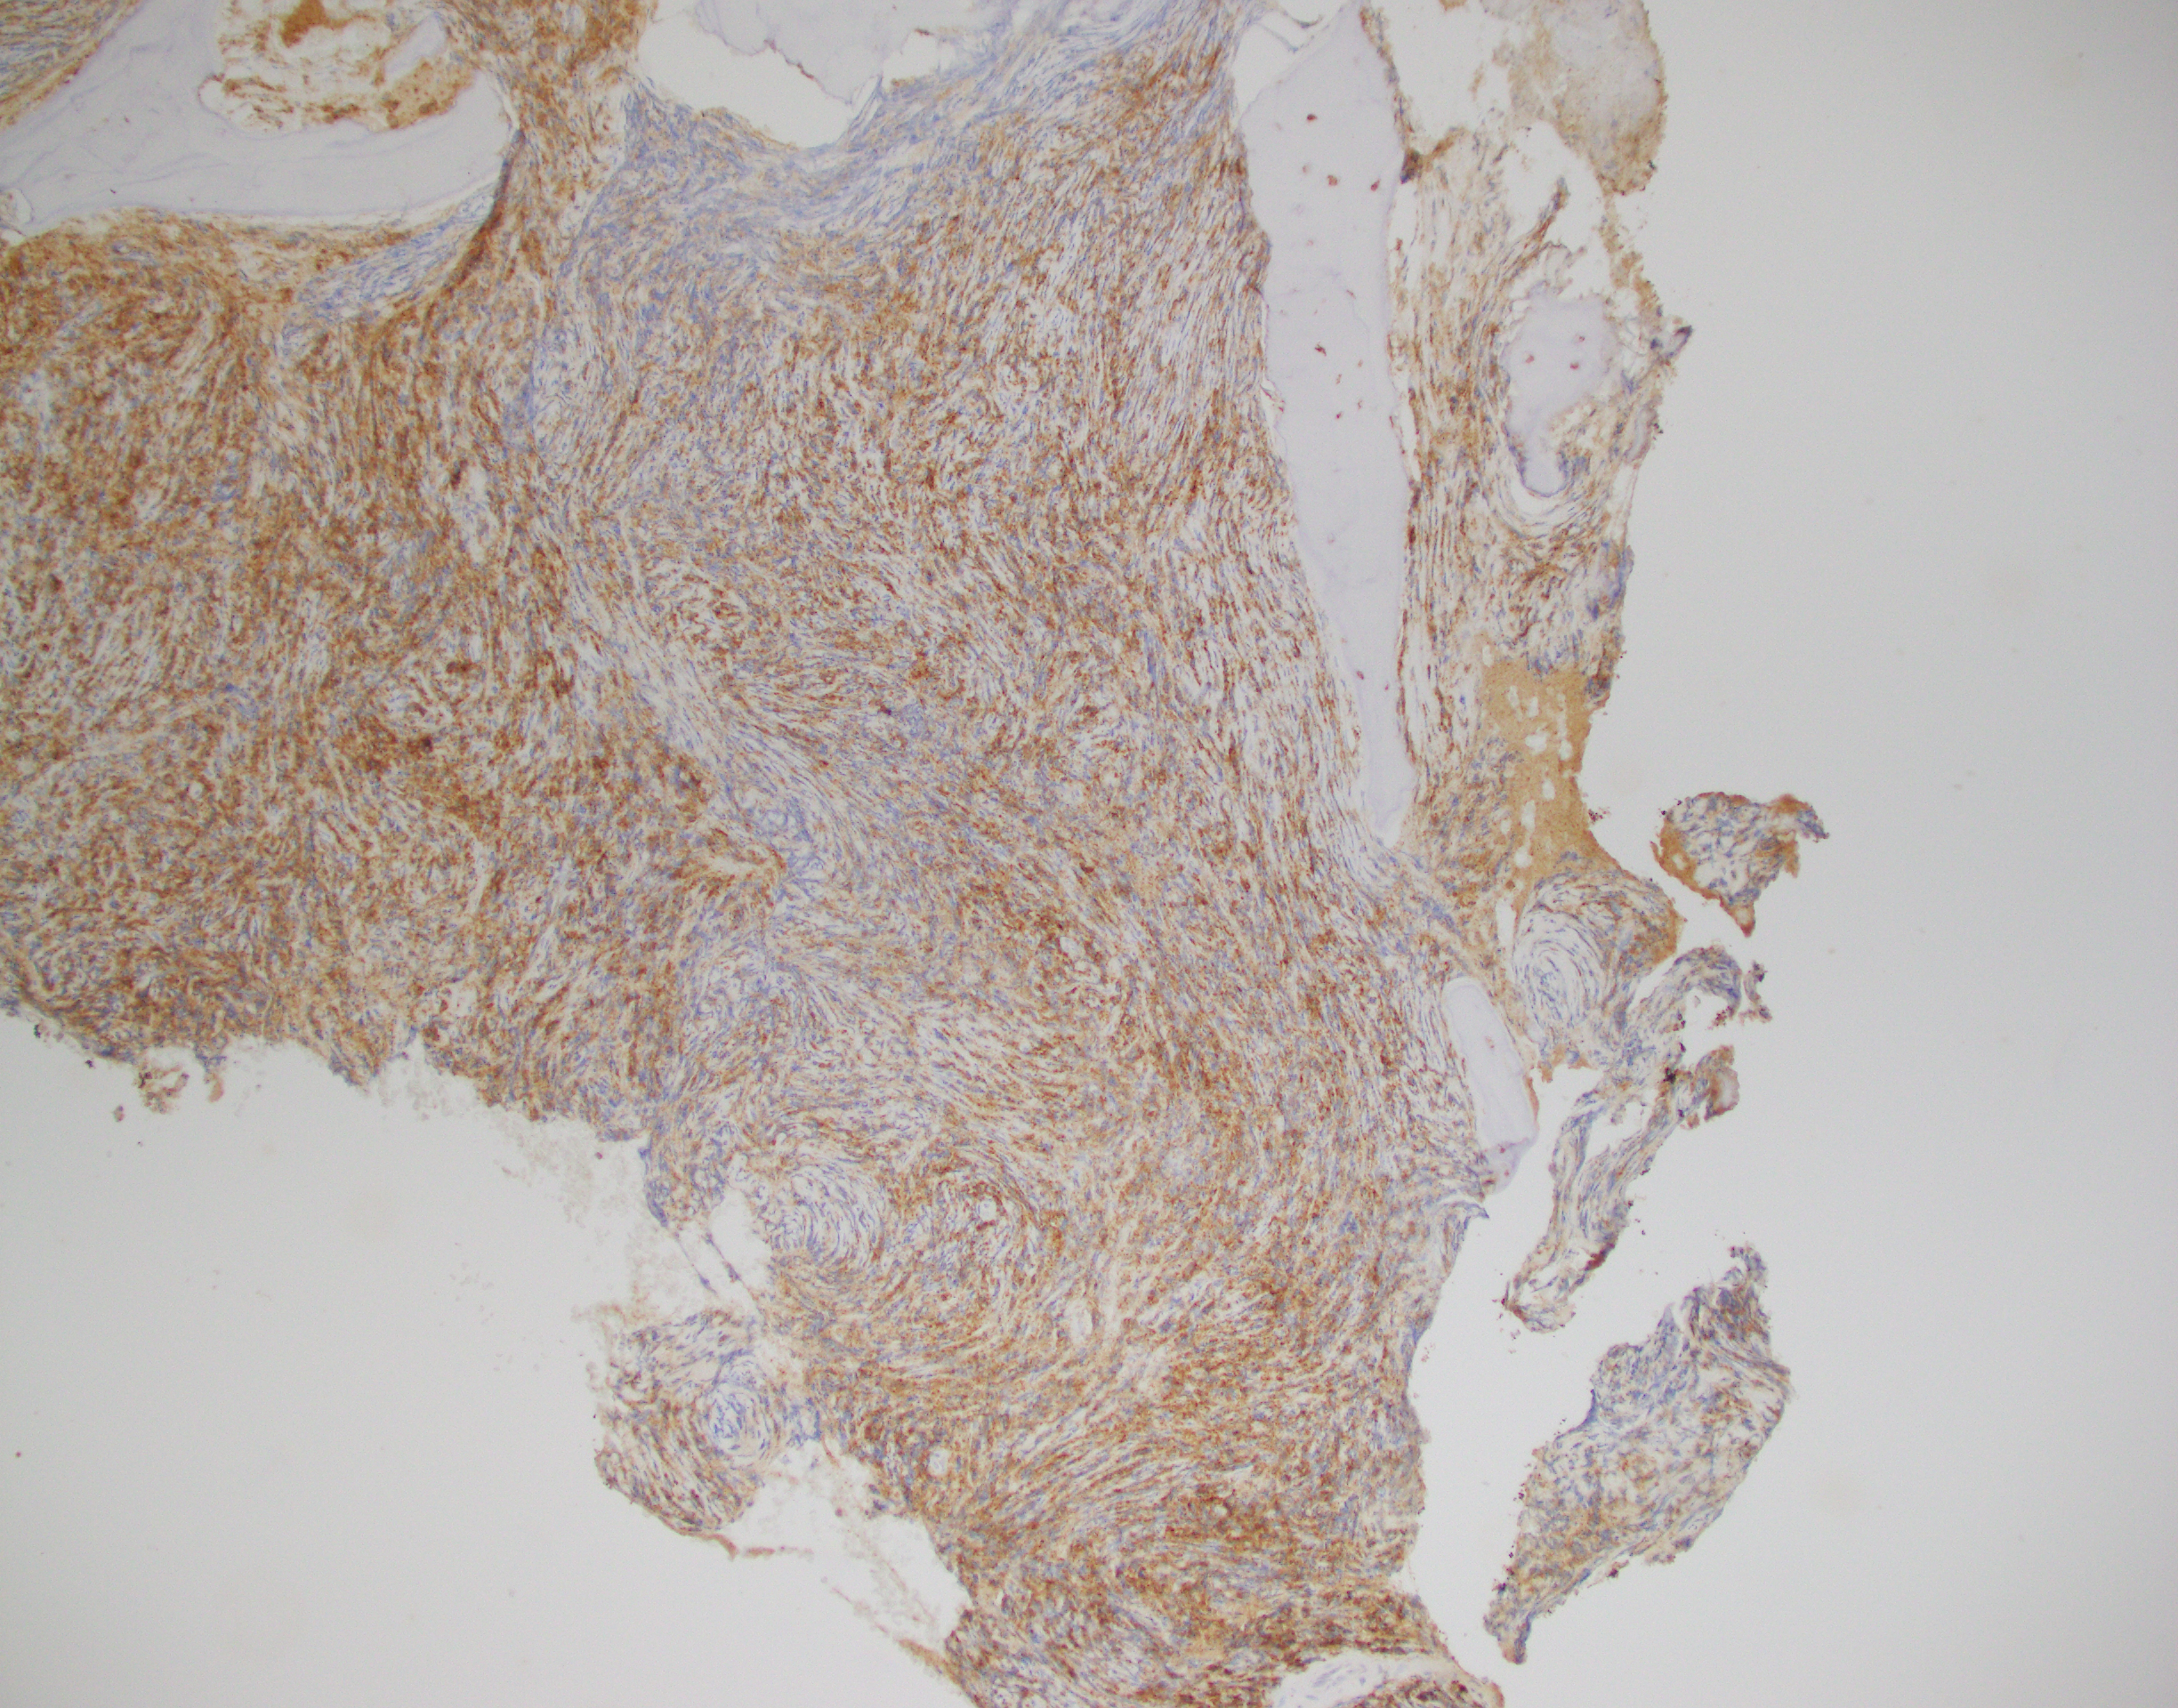

Essentially, this patient was found to have Li-Fraumeni after the second manifestation of an acute sarcoma—the first being osteosarcoma in her teenage years and the second breast cancer in her 30s. Both cancer diagnoses were treated accordingly, and this patient was going through routine work-up for anemia before being referred to the Mayo Clinic. By the time the patient reached there, the clinical investigation included a battery of testing for causes of anemia—all within normal limits—so a bone marrow examination was performed which revealed a significant, though not acute (<20% blasts), myelodysplastic process. A follow-up in-house bone marrow collection revealed hypercellular marrow, now in acute myeloid proliferation, with abnormal myeloid cell maturation and very complex cytogenetics. She had a very complex karyotype and several detectable mutations which were consistent with the WHO’s classification and description of therapy-related myeloid neoplasm as a sequale to the treatments she received for her prior cancers. In the setting of a patient with LFS, it is almost impossible to avoid malignancy. The following slides are a (very abridged) summary taken from my presentation of this patient’s case:

In a case report from 2017 I discussed a patient who had bilateral lung nodules several years after being treated for breast carcinoma. It was initially thought to be relapse but was later correctly diagnosed as de novo peripheral T-cell lymphoma (PTCL). This could have very well been the same clinical scenario, with a different cell lineage. The lesson gleaned here is the same as those ASH/CAP guidelines: stay organized, consistent, and purposeful with your testing and investigation. What came down to a few immunohistochemical markers in this PTCL case could make all the difference in another case. Missing the clinical history and specific genetic mutations present in this LFS/AML patient could have led to a diagnosis of a myelodysplasia related AML instead of a therapy-related one, especially in the setting of such a severe germline pre-disposition.